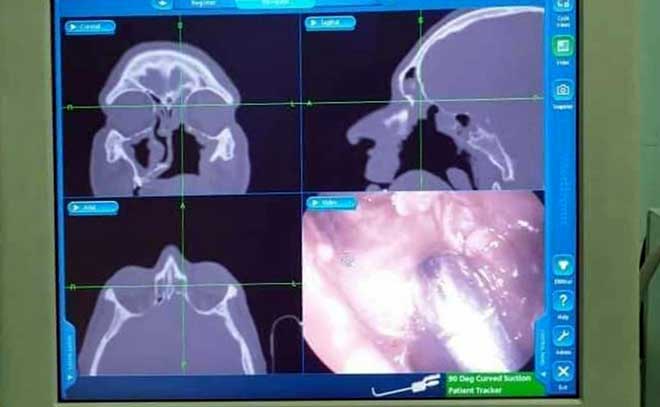

وأشارت الدكتورة الجاسم إلى أنه في المرحلة الأولى جرى تنظيف الجيوب تحت التخدير الموضعي وأخذ خزعات للتشريح المرضي وكانت النتيجة فطارا عفنياً وفي المرحلة الثانية استؤصل الفك العلوي الأيسر ومن ثم أجريت جراحة جيوب تنظيرية مبينة أن صورة الطبقي المحوري بعد العمل الجراحي أظهرت وجود امتلاء بالجيب الجبهي يبدي كثافة معدنية يتماشى مع كرة فطرية معزولة الأمر الذي استدعى إجراء جراحة جيوب تنظيرية موجهة بطريقة الملاحة للتداخل على الجيب الجبهي الأيسر واستئصال الكرة الفطرية ومن ثم تخريج المريض بحالة جيدة.

وتقنية “الملاحة” متوافرة فقط في مشفى دمشق حسب الجاسم واستخدمت كون مكان توضع الكرة حرجا حيث تساعد بنظام تحديد المواقع ونقل الصور لإزالة الانسجة المريضة بدقة مع تجنب إصابة المناطق الحرجة.